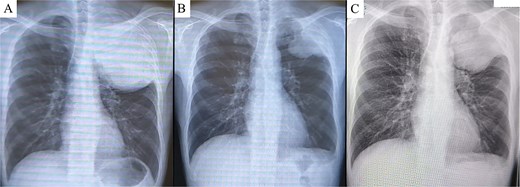

A 45-year-old male presented with left anterior chest pain. A chest X-ray revealed a mass in the left lung. Computed tomography (CT) showed a large tumor measuring 13 × 12 cm occupying the left thoracic cavity, with extensive invasion into the left first through fifth ribs and lung parenchyma. A CT-guided biopsy initially led to a diagnosis of sarcomatoid pleural mesothelioma, and the patient was referred to our hospital. The patient exhibited tumor-associated fever and elevated inflammatory markers. Treatment with nivolumab plus ipilimumab was initiated promptly. A re-evaluation of the biopsy specimen revealed proliferations of short spindle-shaped tumor cells. However, BAP1 was retained, MTAP status was inconclusive, and no CDKN2A/CEP9 probe deletion was observed, ruling out pleural mesothelioma. The final biopsy diagnosis was sarcoma. After four cycles of nivolumab plus ipilimumab, the tumor size significantly decreased (from 139 × 122 mm to 97 × 76 mm), leading to the decision to proceed with salvage surgery (Fig. 1A and B). Despite a 4-week interval between the final immunotherapy dose and the surgery, tumor regrowth was observed during this period (Fig. 2A–C).

Chest X-ray prior to treatment revealed a large mass extending from the left lung apex to the upper lung field (A), which markedly decreased in size following immunotherapy (B). However, during the 4-week interval between the end of immunotherapy and surgery, the tumor demonstrated regrowth (C).